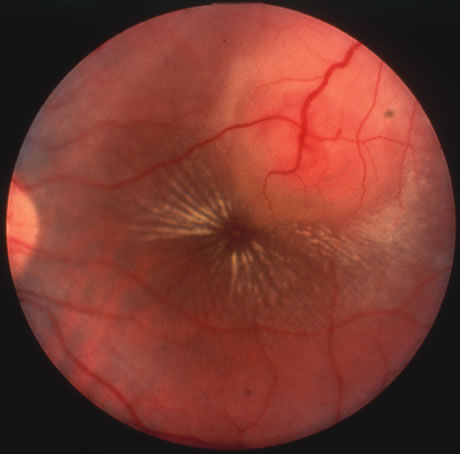

In primary ocular HSV infections, a severe follicular conjunctivitis with regional adenopathy is present. Vesicles may appear on the eyelid skin or lid margin, producing blepharitis (Fig. 3). Corneal involvement initially takes the form of a superficial punctate keratitis, which may progress to dendritic or geographic ulceration. Stromal infiltrates and uveitis are less common and relatively mild in primary disease. In uncomplicated cases, lesions usually heal completely in 2 to 3 weeks without scarring. Most cases of ocular HSV are recurrences. Recrudescent ocular herpes may take the form of dendritic or geographic ulcers, recurrent erosions, interstitial or disciform stromal keratitis, and anterior uveitis.3 HSV may also be an agent of retinitis and acute retinal necrosis (Fig. 4).

Fig. 4. Acute retinal necrosis in the fundus. Note the widespread nature of the involvement.

The acute retinal necrosis (ARN) syndrome is most often caused by the herpes zoster virus, although occasionally it may be a result of herpes simplex infection.12 It is typically described in healthy patients although association with immunosuppressed patients has also been described. Granular, nonhemorrhagic areas of retinal necrosis may be observed in the fundus, often rapidly coalescing with resulting blindness often caused by retinal detachment. There is often an associated vasculitis and vitritis. In immunocompromised patients VZV or HSV retinitis may also take the pattern of progressive outer retinal necrosis (PORN) (Fig. 6). PORN differs from ARN in that the former is multifocal, localized to the outer retina, and is less often associated with vasculitis and vitritis.

Fig. 6. Fundus lesions of progressive outer retinal necrosis (PORN). Note the multifocal lesions.